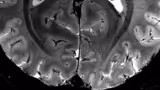

Researchers from Duke University, Harvard, and the University of Otago in New Zealand have developed a novel MRI-based “aging clock” capable of predicting midlife vulnerability to chronic diseases, including the devastating onset of dementia. By analyzing subtle, often invisible changes in brain structure, the tool can forecast a person’s aging trajectory long before outward signs appear.

The tool was then trained using MRI brain scans from these participants at age 45, learning to estimate an individual’s pace of aging using just that single scan.